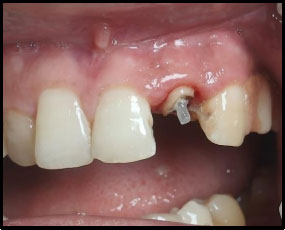

Peeso reamers (sizes 1 and 2) were used for post-space preparation, making sure that 3–4 mm of gutta-percha was retained at the apex. Next, a dual-cure resin cement was used to lute a prefabricated fiber-reinforced post into the canal (Fig. 3). Once the fiber post was in position (Fig. 4). Composite resin was then used to build up the core (Fig. 5). Occlusal view of the core build-up is shown in Fig. (6). Finally, a highly translucent all-ceramic crown was placed, restoring the tooth’s function and aesthetics in alignment with the surrounding dentition in occlusion (Fig. 7) and Occlusal view (Fig. 8).

Post space preparation.

Fiber post in position.